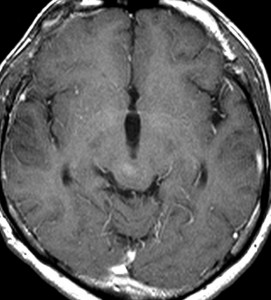

でも腫瘍増大が止められずに,発症1年後に54グレイ30分割の放射線治療を受けています。さらにその半年後くらいから再増大しましたが,スードプログレッションと考えられました。上左MRIは放射線治療前,上右MRIは放射線治療1年後です。毛様細胞性星細胞腫は放射線治療後に一過性増大(多くはのう胞性増大)することが多いです。

のう胞性拡大が止まらず,発症3年後にまた再開頭手術 (left occipital transtentorial approach) で亜全摘出しました。右は術後の画像です。初発時の最初の手術で亜全摘出あるいは全摘出 gross total removalできていればと思える例です。